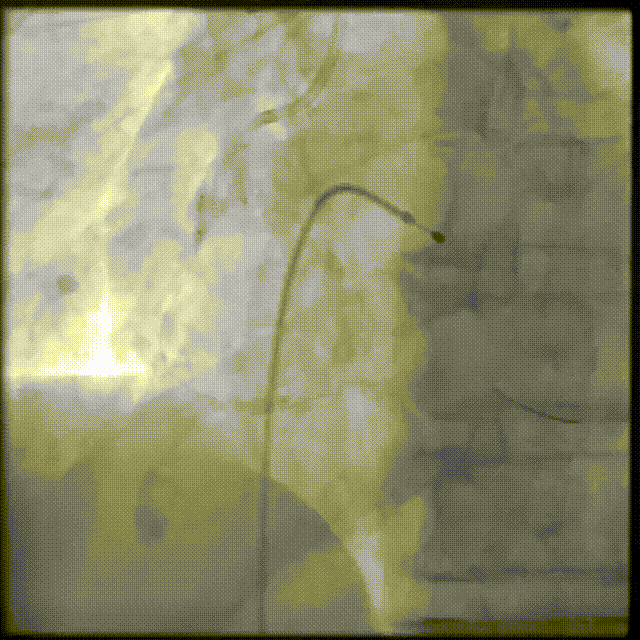

PCI过程-冠状动脉旋切(轨道旋磨)术-1

IVUS导管无法通过,微导管辅助下,将旋磨导丝置于RCA远端,应用1.0mm磨头以13万转反复旋磨钙化病变处(每次15秒,磨头推进速度不超过10 mm/s)

PCI过程-冠状动脉旋切(轨道旋磨)术-2

微导管辅助下,将旋磨导丝置于RCA远端,应用1.0mm磨头以13万转反复旋磨钙化病变处(每次15秒,磨头推进速度不超过10 mm/s)

PCI过程-冠状动脉旋切(轨道旋磨)术-3

共计旋切170秒,术后,狭窄较前减轻